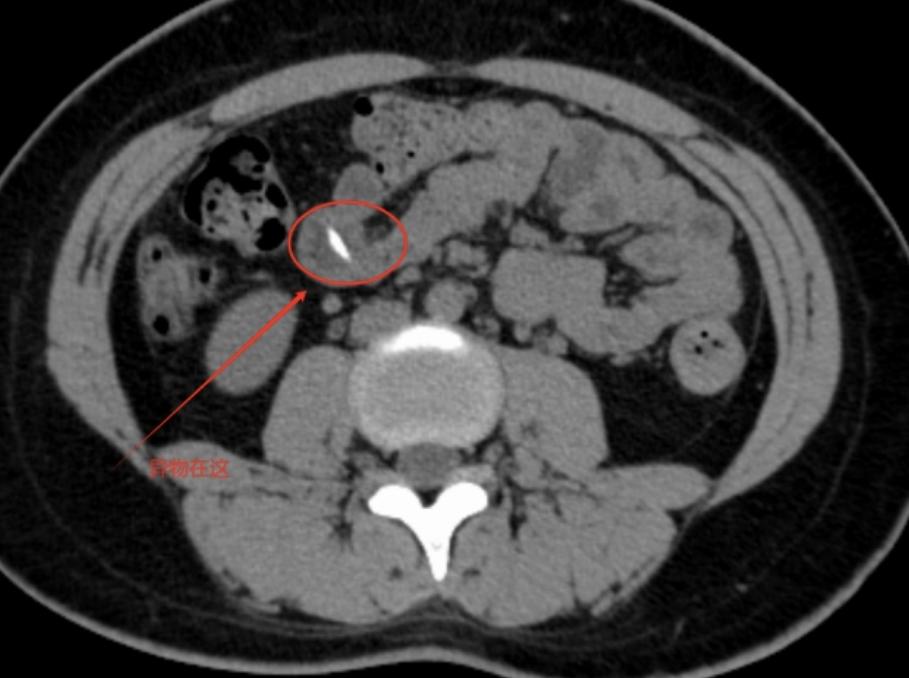

故事要从6天前那顿聚餐说起,家住番禺的小刘(化姓)一家人在外面吃饭,谁知隔天早上,她开始出现上腹隐痛,进食后疼痛加剧,虽休息可自行缓解,但上腹及脐周胀痛症状反复,6月21日,忍无可忍的她来到广东祈福医院普外中心门诊,张永祥副主任医师接诊,腹部CT检查发现:中腹小肠内高密度影,高度怀疑是消化道异物惹的祸,门诊拟“腹痛”收治入院。

中后段小肠腔内卡着的约2cm的棒状异物,两端尖锐刺入肠壁黏膜。管床医生卢嘉豪反复阅片后追问病史,小刘几番回忆才想起几天前在外聚餐,吃了桌上的牛蛙,可能就是当时无意中吃下去的。而这个“牛蛙骨刺客”也是个狠角色,顺着食管、胃一路向下,滞留于小肠。如果不及时处理,可造成小肠穿透性损伤,导致肠穿孔、消化道出血、腹腔感染等严重并发症。

尽管情况紧急凶险,但小刘及家属保守治疗意愿强烈,卢嘉豪医生请示崔东明主任后,先安排禁食、肠道准备、抗感染、补液营养等保守处置方案。严密观察三天过去了,复查CT见异物纹丝不动,腹痛却越来越严重。“这个东西横向卡在小肠内,尖端已经戳破了肠黏膜进去肠壁深层,再拖下去,肠壁被穿透可致肠液漏进腹腔会引发感染。”卢嘉豪医生建议及时手术取出异物。